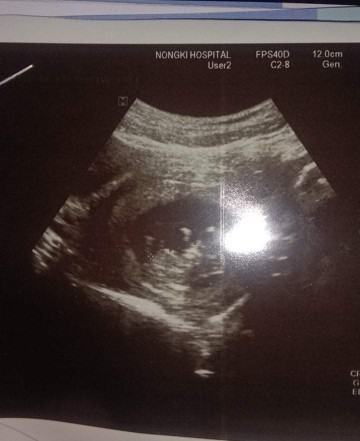

3เดือนแล้วค่ะ..เริ่มเห็นแขน ขา บ้านใหนเหมือนกันมั๊ยค่ะ???3เดือนเห็นชัดขนาดนี้เหมือนกันรึป่าวค่ะ

เห็นเหมือนกันค้ะ